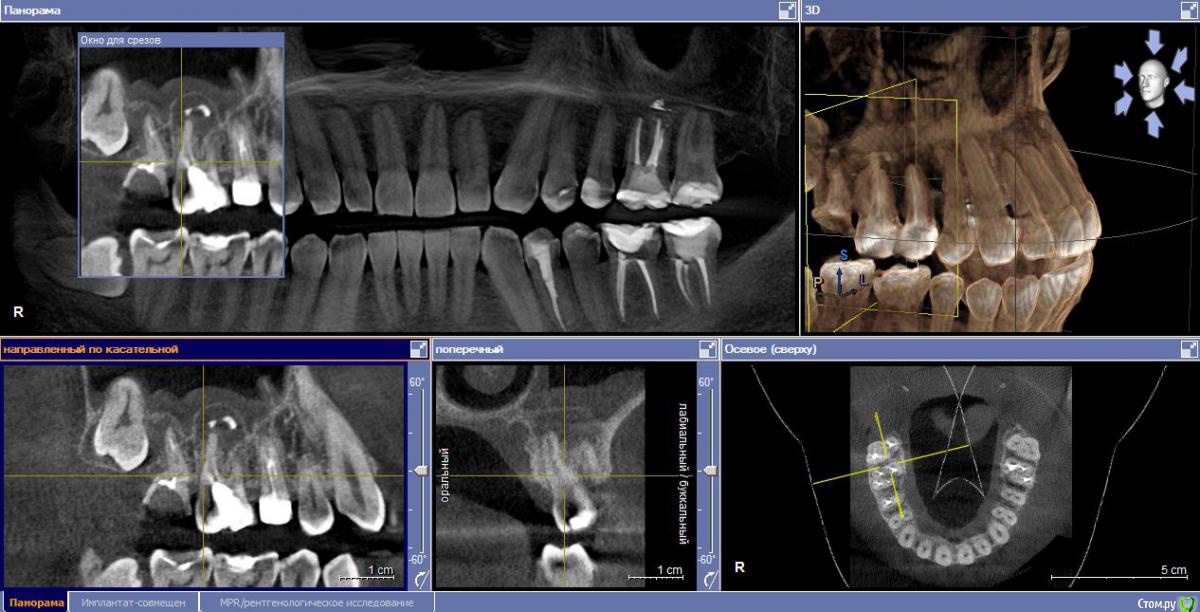

М, 33 года. Есть показания к одновременному удалению 16-го зуба - киста, и 17-го - разрушена верхушка. 8-й предлагают оставить, чтобы "держал кость" (как то так мне озвучили).

Через 3-4 месяца рекомендуют синус-лифтинг и установку двух имплантатов.

- Возможно ли консервативное перелечивание 16 зуба и есть ли смысл?

- Насколько опасная имеется киста?

снимки прилагаю.

и 6 и 7й зубы не выглядят 100% кандидатами на удаление.

1.6 большая вероятность сохранить,но понятнее при очном осмотре и диагностическом вскрытии. 1.7,скорее всего,не жилец,но тоже очно взглянуть на него стОит